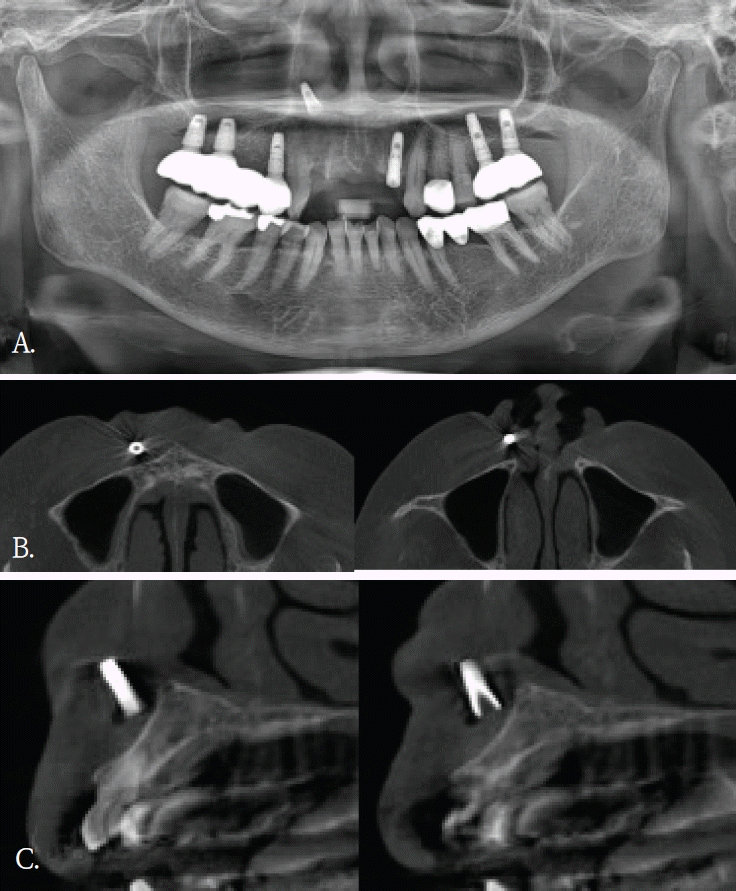

Fig. 2.

A. Panoramic radiograph shows no definite abnormality in the maxilla. B. Axial cone-beam computed tomographic (CBCT) image shows crescent-shaped radiopaque foreign bodies along the anterior walls of the bilateral maxillary sinuses (arrows). C. Cross-sectional CBCT image also demonstrates the same findings on a different plane (arrows).

50대 여자환자가 상악 전치부 임플란트치료를 위해서 콘빔 CT검사를 시행하였다. 파노라마방사선영상에서는 해당 부위에 특이 소견이 뚜렷하지 않았다(Fig. 2A). 그러나 콘빔CT의 축상면 및 횡단면 영상에서 양측 상악동 전벽에 인접한 안면 피하 연조직을 따라, 반달모양의 경계가 명확하고 내부가 균질한 음영을 보이는 구조물이 관찰되었다(Figs. 2B and C). 해당 소견은 주된 촬영 목적과 무관하였고 양측에서 대칭적으로 관찰되었으며 관련 증상이 동반되지 않았다. 임상 소견 및 영상 소견을 종합할 때 병변 가능성은 낮다고 판단하였고, 위치와 형태를 고려하여 피하에 주입된 미용필러에 의한 소견으로 판단하였다. 이에 추가 처치는 시행하지 않았다.- 증례 3

콘빔CT는 해부학적 구조물이나 이물질 위치를 확인하고, 인접 구조물과의 관계를 파악하는데 유리하다. 2차원 영상에서 발생되는 중첩을 줄이고, 3차원적인 위치정보를 제공함으로써 치과 임플란트 치료계획이나 치아 교정 진단과정에서 필수적인 영상검사이다. 또한, 임플란트 식립이나 매복치 발거등 외과적 치료과정에서도 진입 경로 결정에 도움을 주어 술 후 합병증을 감소시킨다.콘빔CT의 원래 촬영 목적과는 관계없이, 우연히 발견되는 소견들이 있다. 이러한 소견의 빈도는 24.6~94.3%로 보고마다 매우 다양하다[1,2]. 소아 및 청소년연령군에서의 빈도도 0.4~80.3%로 다양하지만 매우 자주 발견된다[3]. 발견되는 부위는 치아 및 치조골을 벗어난 부위가 대부분으로 주로 부비동 및 비강, 혈관, 연조직, 경추이다[1-3]. 그러므로, 콘빔CT 검사할 때 촬영목적 부위 뿐 만 아니라 그 외 다른 부위의 판독도 충분히 이루어져야 한다[2,4,8]. 특히 어린 환자에서는 방사선방어를 고려하여, 관심부위 뿐 만 아니라 콘빔CT영상에 포함된 모든 부위에서 영상판독이 충분히 이루어져야 한다[3]. 우연히 발견되는 소견의 양상도 매우 다양하다. 부비동 및 비강에서는 점막비후, 점액저류낭, 비중격만곡이 많이 발견되고, 혈관부위에서는 경동맥석회화가 주로 발견된다. 연조직에서는 편도석, 경동설골인대골화가 주로 발견되는 소견이다[1-3]. 대부분 해부학적 변이이거나 의학적 조치가 필요하지 않은 경우이다.하지만 추적검사나 치료가 필요한 임상적으로 의미가 있는 소견들도 매우 다양한 빈도로 발견된다. 최소 0.4%에서 최대 37%까지로 전체의 약 1/6-1/3 정도에서 발견되어 주의깊은 콘빔CT 영상판독이 필요하다. 이들 소견중에는 치근단병소, 치성낭, 종양도 있었으며[1-3], 오랜 기간 동안 인지하지 못했던 이물질도 발견된다[1,4,6,8].우연히 발견된 이물질들은 치조골 및 악골 부위가 아닌 다른 부위에서 많이 관찰되었다. 교정목적으로 촬영된 콘빔CT에서 비강내에 플라스틱 이물질이 우연히 발견되어 이비인후과 의뢰 후 이물질을 제거한 증례보고가 있다[4]. 증상이 없어서 이물질의 유무를 알 수 없었지만, 콘빔CT에서 비강내 이물질이 확인되어 외과적으로 제거한 증례보고도 있다[5,6]. 증상이 있어 촬영한 상악 견치 치근단방사선사진에서 모호한 방사선불투과성 이물질이 관찰되어, 이후 촬영한 콘빔CT에서 이물질이 유리조각으로 확인된 증례보고도 있다[8]. 이 증례는 유리같은 이물질은 치근단이나 파노라마방사선사진에서는 명확하게 관찰되지 않았기에 콘빔CT검사가 매우 유용하였던 경우이다.증례 1에서도 초진시 파노라마영상에서는 유리조각을 관찰할 수 없었기에 연조직 병변으로 진단되었으나, 재내원후 촬영된 콘빔CT영상에서 연조직내에 있었던 이물질임으로 확인된 경우이다. 윗입술에 있었던 유리조각이 방사선불투과성 물질이였지만, 상악 전치부와 중첩되어 파노라마방사선영상에서 뚜렷하게 구분되지 않았다.증례 5와 같이 파노라마방사선영상에서 모호하게 관찰되었거나 증례 3과 4같이 파노라마방사선영상에서 협-설위치를 명확하게 알 수 없었던 경우, 콘빔CT영상에서 임상적으로 의미있는 이물질임을 확인되었고 외과적 치료가 시행되었던 증례들이다. 특히, 이들 소견은 악골이 아닌 안면 연조직 부위에서 관찰되어, 주의 깊은 영상판독의 중요성을 다시금 일깨워 준다.한편, 안면미용시술을 받은 환자들이 치과에 많이 내원하면서 우연히 발견되는 이물질 소견 중 하나가 미용 필러이다[9]. 치과의사들에게 아직은 익숙하지 않은 방사선영상 소견이고 부위도 치아나 악골이 아닌 연조직부위에서 관찰되기에 영상 판독에서 배제될 가능성이 있다. 미용필러도 파노라마방사선 영상에서보다는 콘빔CT영상에서 위치나 형태, 양상을 잘 관찰할 수 있다.본 증례들은 파노라마방사선영상에서 인지되지 않았던 이물질 3증례와 파노라마방사선영상에서 의심된 이물질이 콘빔 CT에서 위치와 형태가 명확히 규명된 2증례를 포함한다. 이를 통해 악안면 콘빔CT 판독 시 촬영 목적 부위에 국한하지 않고 영상에 포함된 전체 영역을 체계적으로 검토함으로써, 이물질과 같은 우연히 발견되는 소견이 누락되는 것을 줄일 수 있음을 알았다. 또한 추가 촬영이나 불필요한 검사로 인한 방사선 노출을 예방하여, 콘빔CT 검사의 정당성과 임상적 유효성을 강화하는 뒷받침이 됨을 알았다.